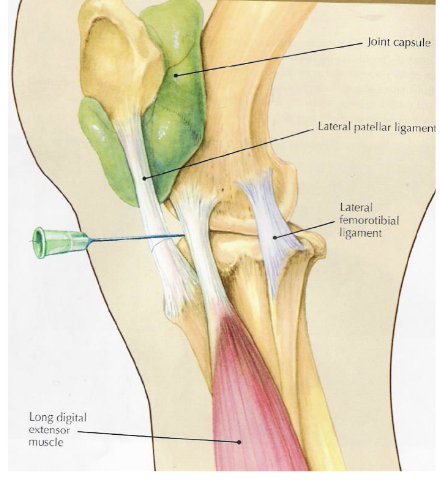

stifle

bones- patella, distal femur (+ medial and lateral trochlear ridges), tibia

lateral trochlear ridge of femur is shorter and smaller than medial

soft tissue structures- 3 patellar lig (medial middle lateral), medial & lateral collateral lig

joints- femoropatellar, medial femorotibial, lateral femorotibial

what is desensitized with a femoropatellar joint block

joint, in 65% of horses it can communicate w/ medial femorotibial joint but youre never sure which horses so you treat them all separately

what is desensitized with a lateral femorotibial joint block

joint